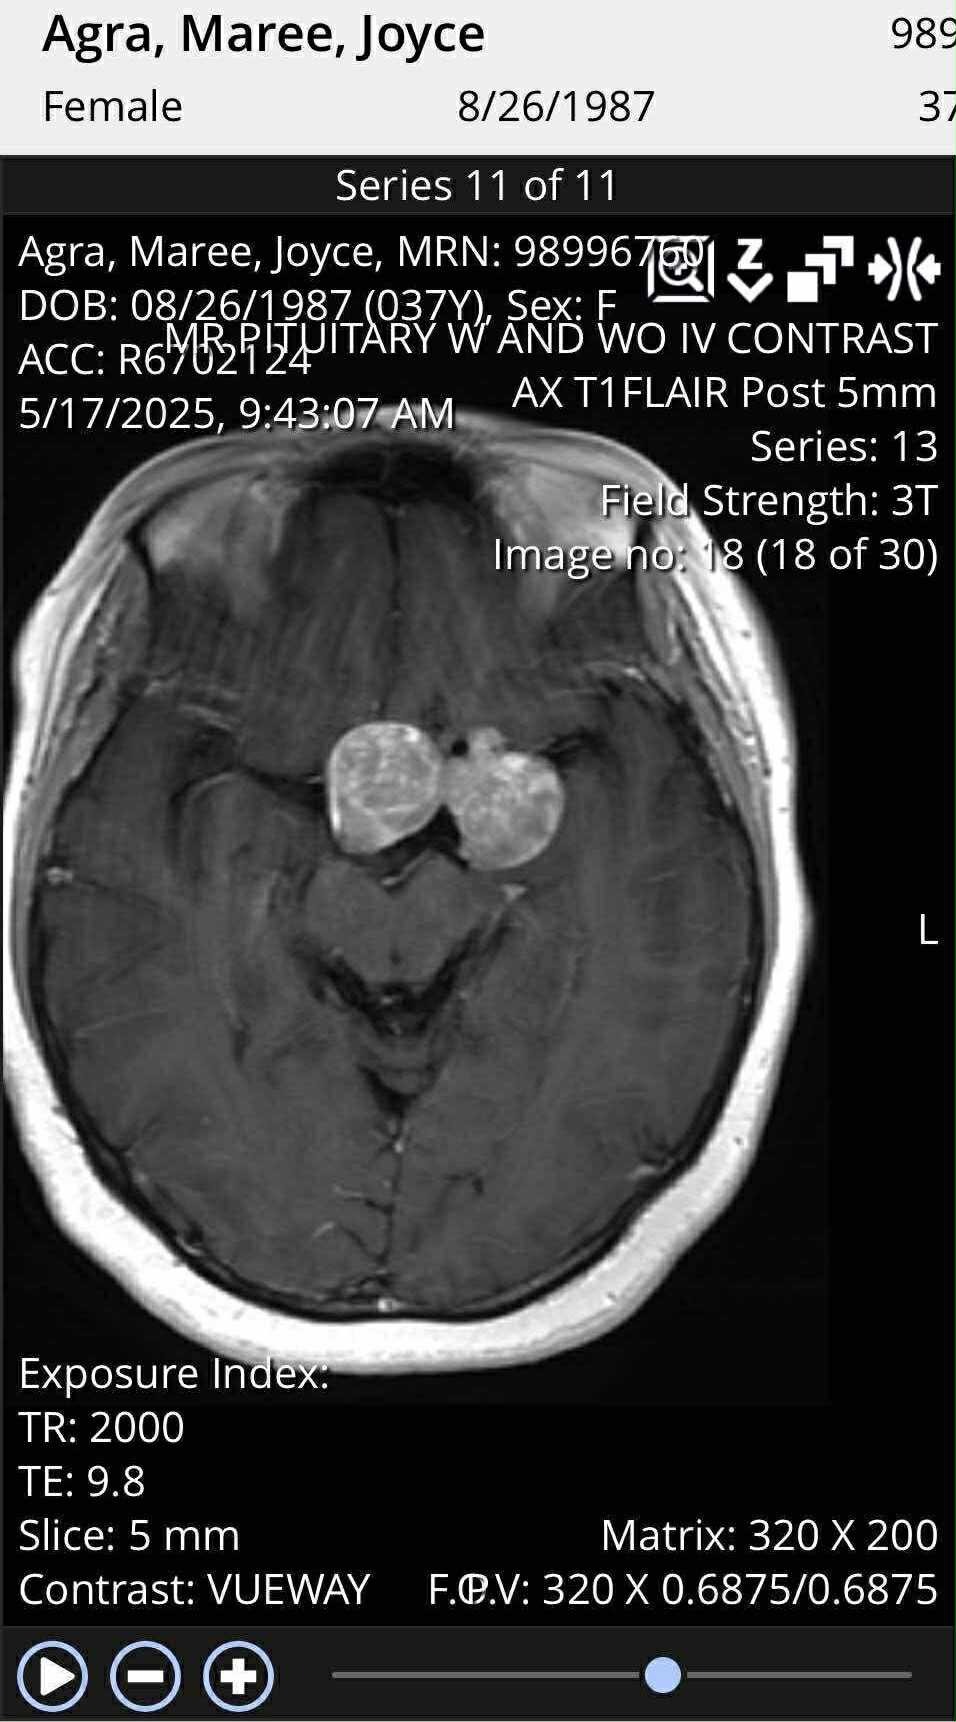

Help Joyce Continue Her Fight Against a Brain Tumor – Support Needed for Ongoing Care

Joyce is one of the strongest, kindest, and most radiant souls I know. She’s also a devoted young mother of two beautiful daughters. Her life was turned upside down when she was diagnosed with a 5cm brain tumor. Despite the fear and pain, she faced brain surgery with incredible courage. But the fight isn’t over—the doctors were unable to remove the entire tumor, and Joyce is now preparing for the next stages of her treatment: radiation, hormone therapy, and extensive recovery.